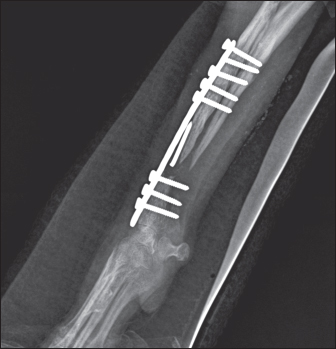

Fig. 4. Mediolateral and craniocaudal radiographs of antebrachial bones, 9 weeks after the revision surgery showing very good cortical graft bridging.

During the control examination by the 9th post-operative week, the weight bearing with the limb was steady, whereas lameness, pain, and swelling were absent. Radiologically, an excellent bridging of the cortical graft without loosening of fixation implants was demonstrated (Fig. 4).